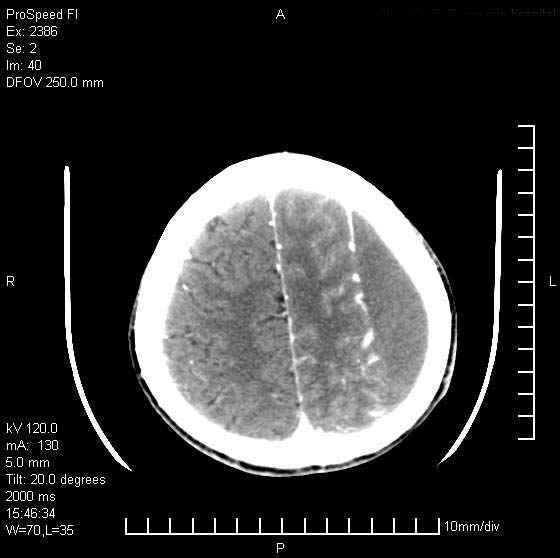

以下是引用天南地北在2007-9-19 18:43:00的发言:[br]典型慢性硬膜外血肿[br][br][本贴已被 天南地北 于 2007-9-19 18:44:11 修改过]

以下是引用曼一拍在2007-9-20 11:06:00的发言:[br]支持慢性硬膜下血肿.[br]慢性硬膜下积液:血肿有包膜,ct值稍高于脑脊液,增强可有染色。不典型者血肿可多呈梭形.是硬脑膜与蛛网膜之间的潜在腔隙内的血肿。[br]鉴别:[br]1\\硬膜外血肿:是颅脑外伤后脑膜或板障内血管破裂,血液在颅骨与硬膜之间积聚所致.通常是脑膜动脉破裂,也可因静脉窦破裂或颅骨的板障静脉出血,发生于外伤的着力部,常与颅骨骨折并存。脑膜动脉出血则急,若是板障静脉出血在则可有慢性。[br]2\\硬膜下积液:(硬膜下水瘤)[br]是由于蛛网膜破裂,脑脊液经蛛网膜破口进入硬膜下腔不能回流。或水肿阻塞而形成。[br]ct表现:颅骨内板下方新月形低密度区近似脑脊液密度;占位效应清,周围无脑水肿。[br]